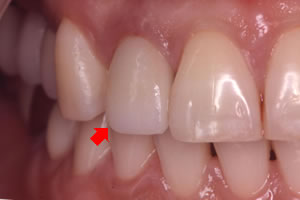

症例4![]() インプラント挿入後

![]() レントゲン写真